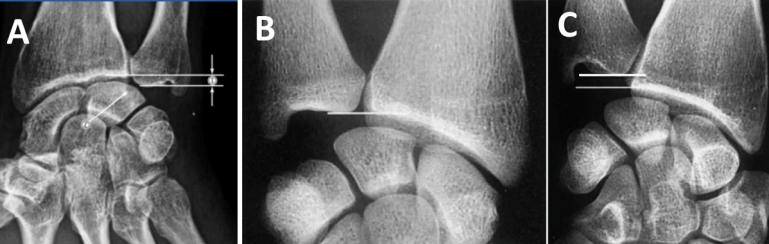

3. Hội chứng xung đột bên trụ (ulnar impaction syndrome): khi xương trụ dài hơn xương quay, có thể làm cho nó “va vào” các xương cổ tay nhỏ hơn (hình dưới).

Hình A: Xương trụ dài hơn xương quay gây ra hội chứng xung đột bên trụ.

Hình B: Xương trụ dài bằng xương quay.

Hình C: Xương trụ ngắn hơn xương quay.